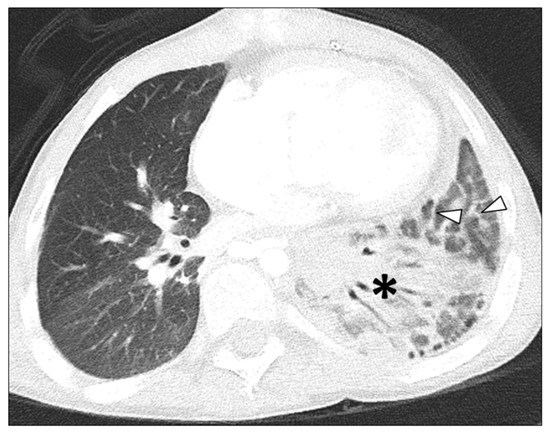

3.2.1. Lung Findings on Thoracic MDCT Study

3.2.2. Pleural Findings on Thoracic MDCT Study

| Consolidation | 16/19 (84.5%) | 3/45 (6.7%) | <0.001 |

| Septal Thickening | 16/19 (84.5%) | 36/45 (80%) | 1.000 |

| Pleural Thickening | 17/19 (89.5%) | 37/45 (82.2%) | 0.710 |